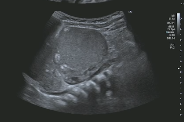

2岁 女孩,右腹部肿块

| 脊柱两侧病变活检 |

病理:神经母细胞瘤